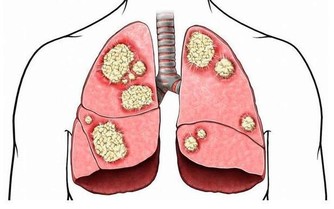

2. 全世界最不好的習慣是抽菸

抽菸的人,氣管炎,肺氣腫,肺心病,最後肺癌,這是死亡三部曲。